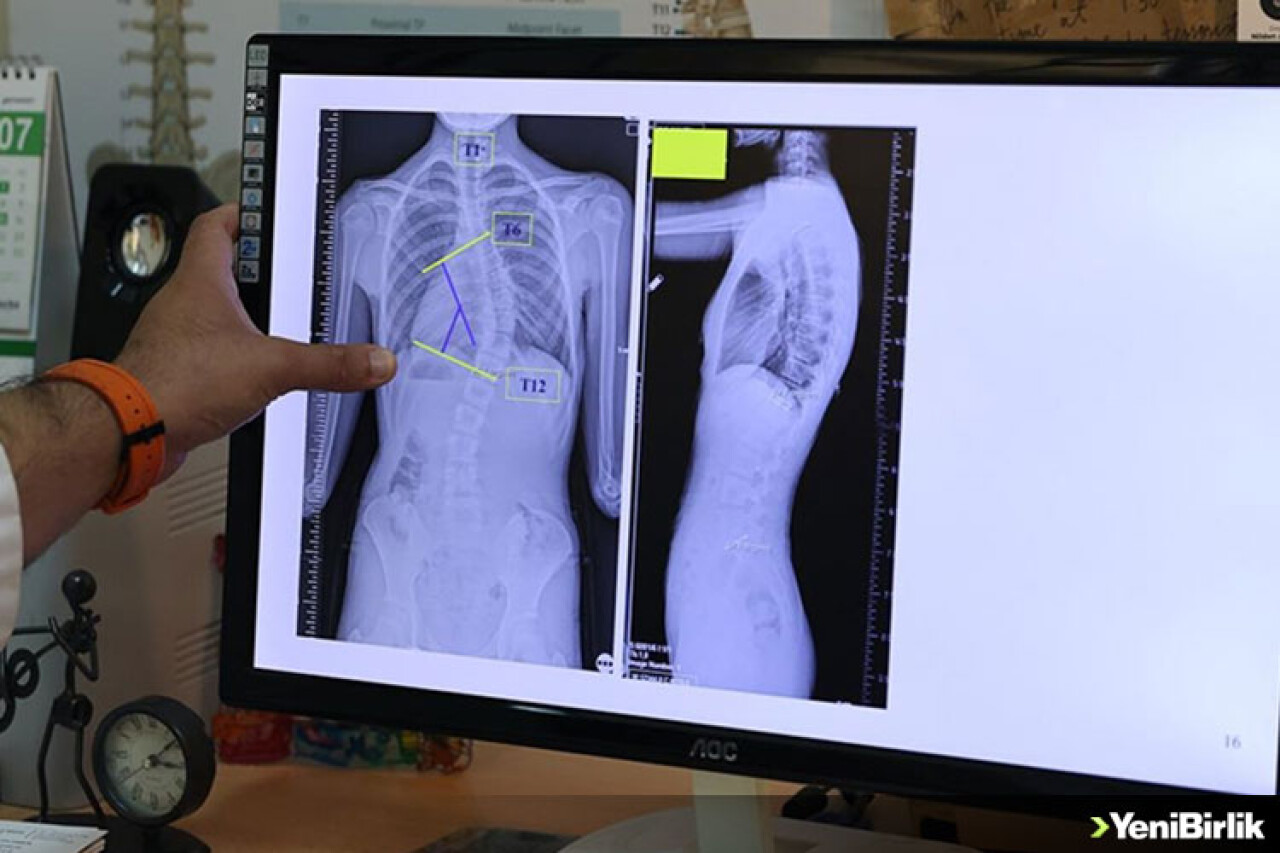

Doç. Dr. Coşkun, omurganın ön ve arka planında 10 dereceden fazla olan eğriliği skolyoz hastalığı olarak kabul ettiklerini belirtti.

Coşkun, skolyozun genellikle 10-19 yaş aralığında görüldüğüne işaret ederek, "Skolyoz, nedeni bilinmeyen bir hastalıktır. Ergenlik, adölesan idiopatik skolyozun en sık görülen yaş grubunu oluşturmakta. Şikayetler genelde omuzların bir tarafında yükseklik farkı olması, bir omuzun daha yukarıda yerleşmesi. Ayrıca hasta öne doğru eğildiğinde, hastada bir tarafında sırtında bir yükseklik, bir kamburluk bulgusu olması. Bu yükseltinin bir tarafta belirginleşme, diğer tarafta silinme, skolyozun ana bulgularındandır." dedi.

"Skolyoz hastalığında tedavilerden biri gözlem tedavisidir. Gözlem skolyozda bir tedavidir. Biz gerçekten de 0 ila 20 derece arasındaki eğriliklere pek bir şey yapmayız. Bu çocukların gelişimini takip ederiz ve erişkin yaşa geldiğinde de bu tedaviyi sonlandırırız. Artık bu çocukların bir riski, hastalığın ilerlemesi açısından yoktur. 20 ila 40 derece arasında ise ya da 45 dereceye kadar biz çocuğun yaşı eğer uygunsa korse tedavisi uygularız. Korse tedavisi için çocuğun büyümesinin devam etmesi lazım. Kemik yaşı tamamlan, büyümesi tamamlanmış bir çocukta korse tedavisinin yeri yoktur. 45 dereceyi aşan eğriliklerde ise eğriliğin her sene ilerleyeceğini öngörerek cerrahi tedavi uygulamaktayız."